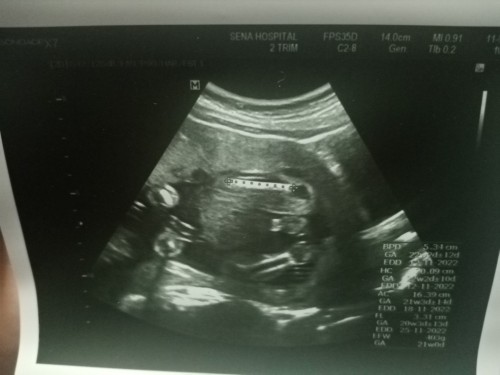

พฤศจิกายน 20w6d

ทีมพฤศจิกายน ยังไม่รุ้เพศชัดเลยคะ แต่หมอเดาว่าน้องเป็นผู้หญิง แม่ๆได้ ผู้หญิงหรือผู้ชาย กันบ้างคะ 20w6d